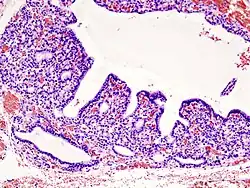

Hyperplasia of the thyorid follicles in hyperthyroidism, H&E staining.